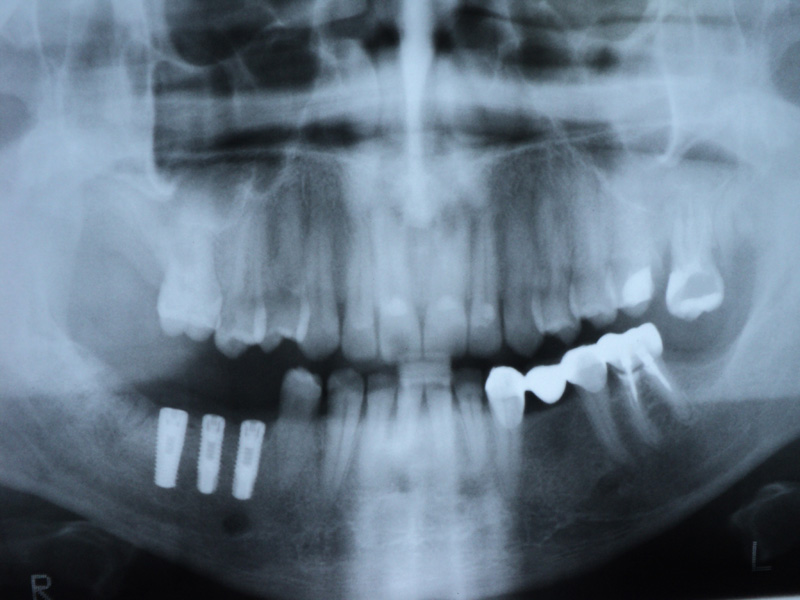

Implante - Galerie Foto

Caz I